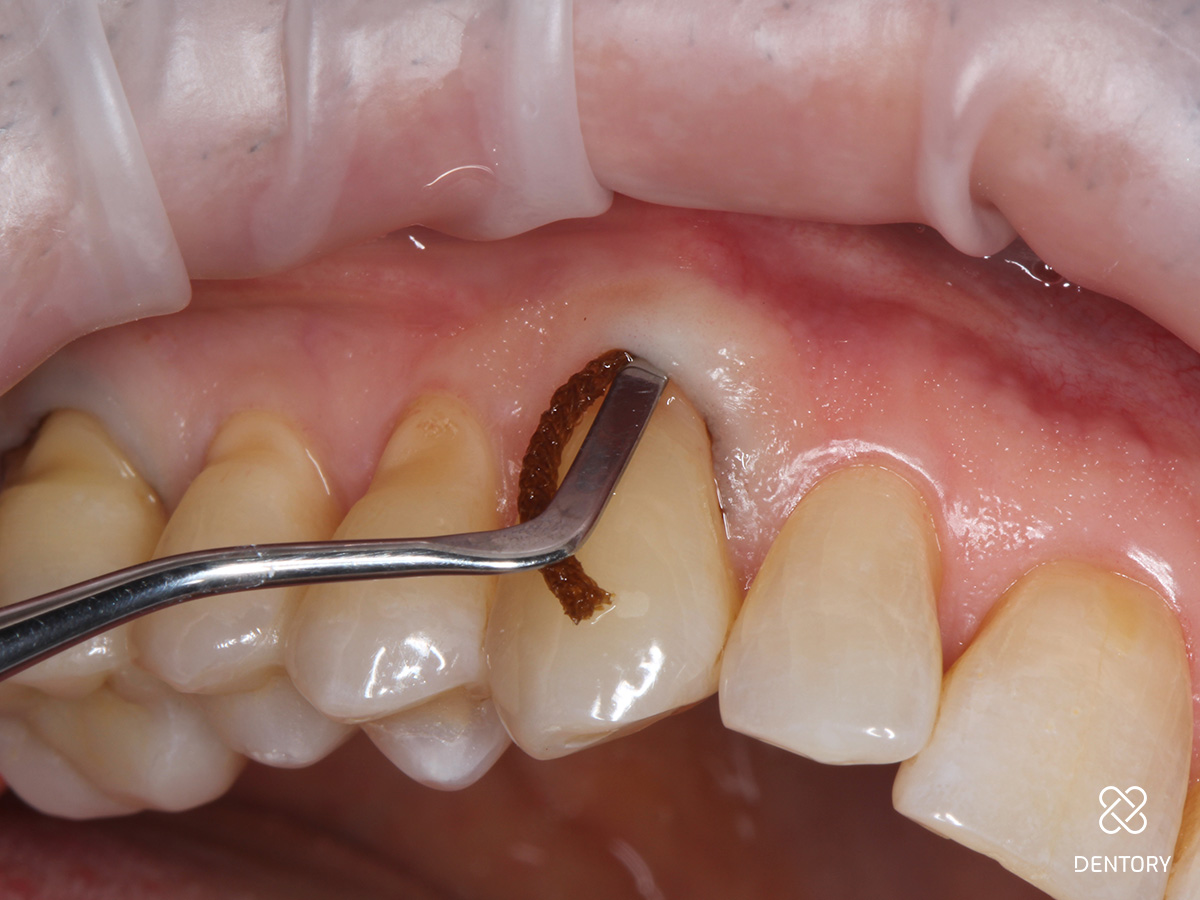

Abbildung 2

Beurteilung der Lage der Kavität nach zervikal. Liegt der Defekt supragingival, kann auf den Sulkus-Faden verzichtet werden. Liegt der Defekt äquigingival oder subgingival wird ein 00-Faden gelegt.